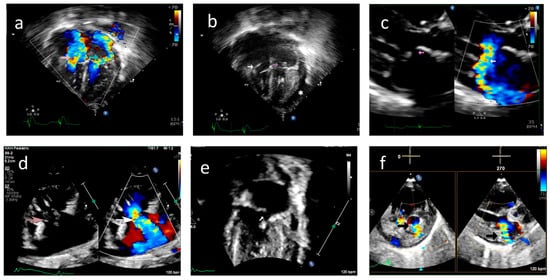

However, on day 45 of life, the baby developed acute respiratory distress and lactic acidosis, requiring inotropic infusion. The septic workup was negative; however, anti-Ro titers were positive. An echocardiographic evaluation showed moderate TR and severe MR. Flail mitral and tricuspid valve leaflets were noted with ruptured chordae resulting in valve prolapse and severe regurgitation (Figure 4/Videos S6–S11). Pleural and pericardial effusions were present with hepatic dysfunction and seizures while on steroids and inotropic supports. The neonate expired at 55 days of age.

Figure 4.

Case A: (a) Echocardiogram, four-chamber view with color doppler showing severe tricuspid regurgitation (pink arrow) and severe mitral regurgitation (green arrow) noted on day 45 of life. (b) Echocardiogram, four-chamber view, demonstrating ruptured chordae resulting in prolapse of tricuspid valve leaflets (white arrow) and mitral valve leaflets (pink arrow). *—Pericardial effusion. (c) 2D and color doppler long axis views of the mitral valve showing valve prolapse (pink arrow in 2D image) and severe mitral valve regurgitation (white arrow in color image) (d) Modified long axis view on a 2D echocardiogram, showing rupture of the tricuspid valve chordae (pink arrow) and severe tricuspid regurgitation (white arrow). (e) Echocardiogram, four-chamber view of ruptured mitral valve leaflet chordae causing mitral valve prolapse (white arrow). (f) X-plane color doppler image on a 2D echocardiogram showing severe mitral regurgitation (black arrow).